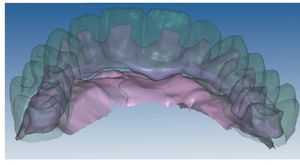

Mediante el uso de un escáner óptico de luz estructurada, los protocolos CAD registran los primeros datos relativos al modelo maestro con las correspondientes posiciones de implante (figs. 87 y 92). En el siguiente paso tiene lugar la digitalización de la planificación, previamente realizada en cera de escaneo matificada, de la restauración definitiva (figs. 88, 90 y 93). La subsiguiente conciliación de los datos mediante el uso del software de diseño dental permite al protésico planificar virtualmente el resto del procedimiento (figs. 89 y 91, 94 a 96) a partir del diseño de las estructuras (figs. 97 y 98).

Fig. 90. La posición de los implantes en relación con la planificación.

Figs. 94 a 95. Planificación CAD de la estructura del maxilar inferior, en representación lingual y vestibular.

Figs. 96 a 98. El diseño definitivo de la estructura del maxilar inferior, desde distintas perspectivas.